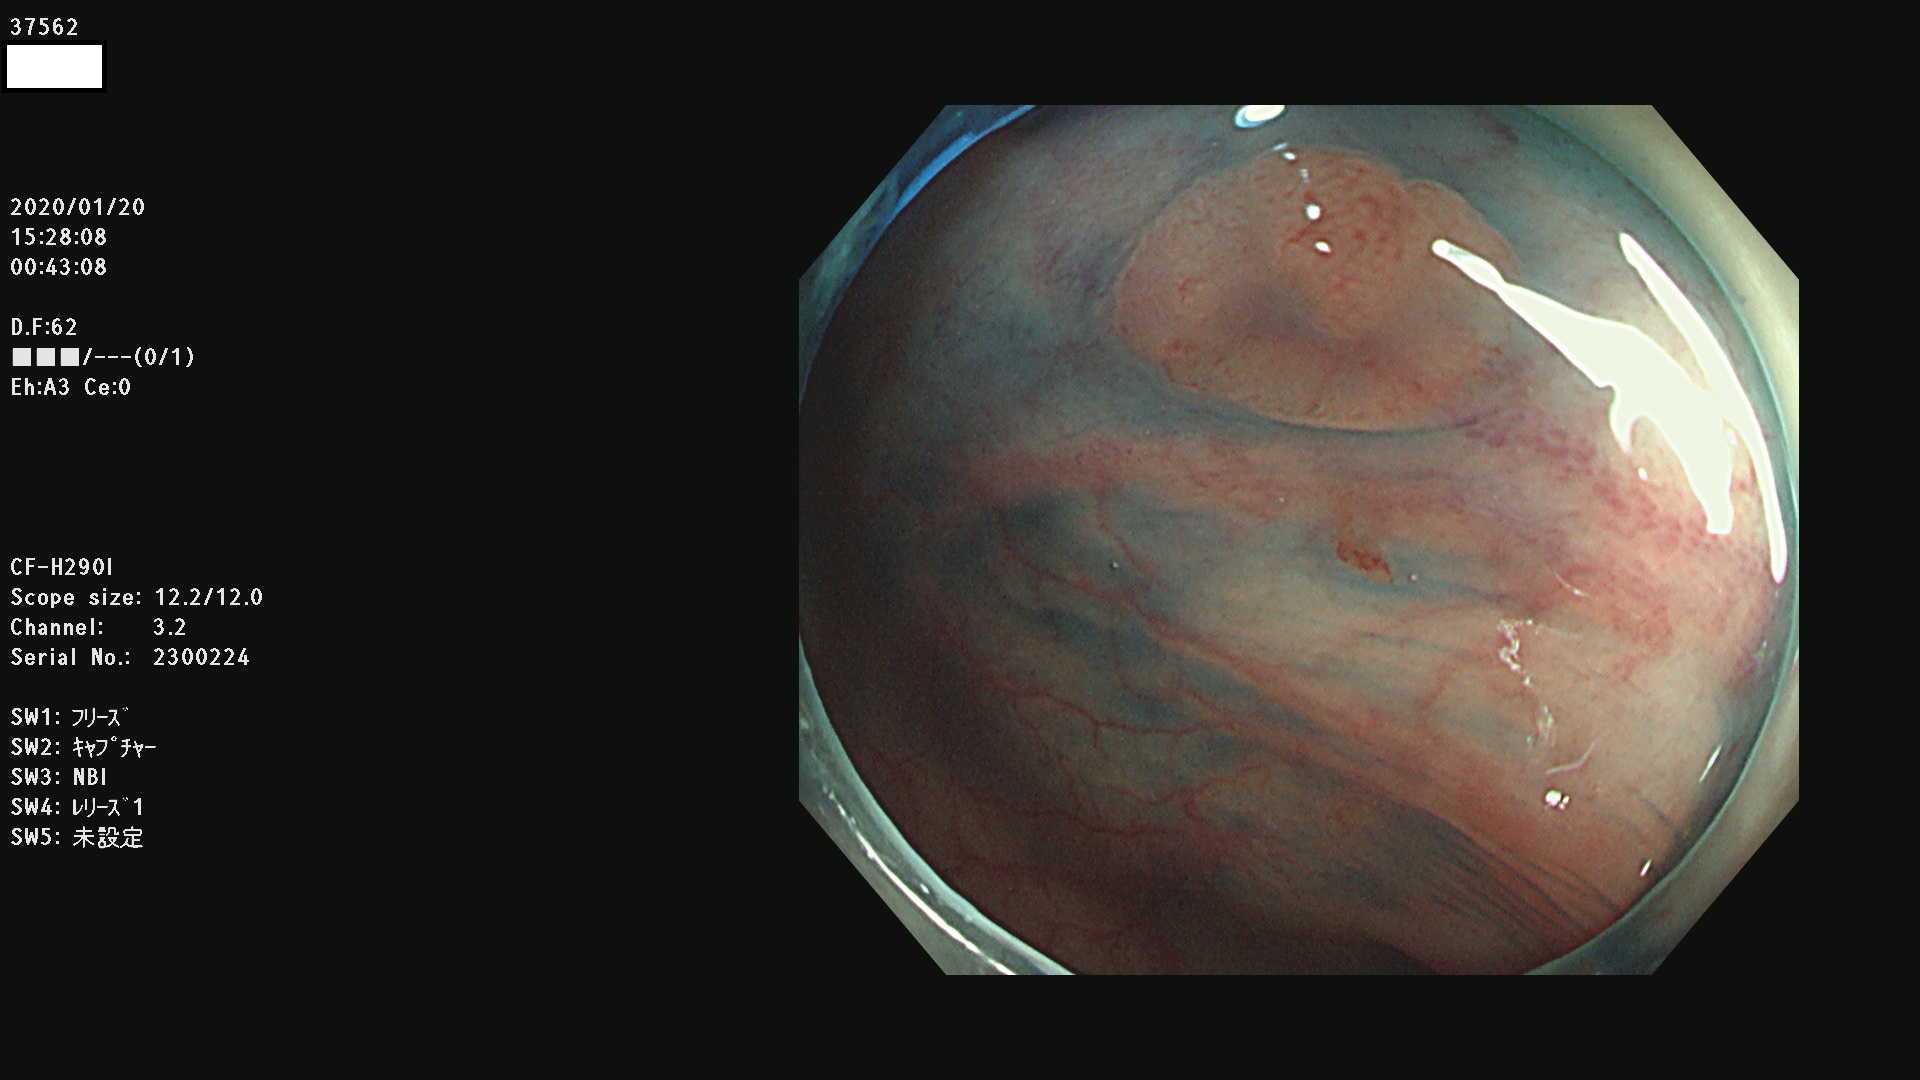

腺腫発見率 67 % (カルテ番号 37500〜37599の100名の方の検査結果で集計)大腸癌検診最新情報

以下のカルテ番号の方に腺腫(Adenoma,Group3〜5)が見つかりました(集計法)

37500 37502 37503 37505 37508 37509 37510 37511 37512 37513 37514 37517 37519 37520 37521 37525 37526(SSAPのみ) 37527 37528 37529 37531 37532 37533 37534 37536 37538(SSAPのみ) 37539 37541 37542 37543 37547 37548 37549(SSAPのみ) 37550 37552 37555 37556 37561 37562 37563(SSAPのみ) 37564 37565 37566 37567 37568 37570 37571 37572 37573 37574 37575(SSAPのみ) 37576 37577 37579 37580 37582 37583 37586(SSAPのみ) 37587 37588(SSAPのみ) 37590 37593(SSAPのみ) 37594 37596 37597(SSAPのみ) 37598 37599

発見困難で危険性の高い平坦型病変(上記100名より抽出) ![]()